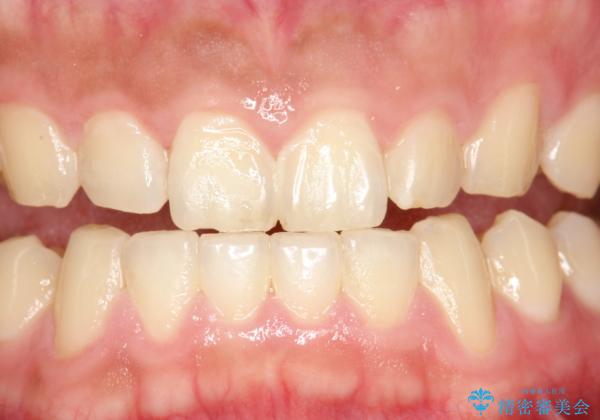

歯科衛生士によるクリーニング PMTC

- 半年ぶりの来院で、全体的なチェックとクリーニング希望でした。PMTC(自費クリーニング)60分コースを行いました。

PMTCとは、プロフェッショナル(歯科衛生士)メカニカル(機械的)トゥース(歯)クリーニング(清掃)の略です。歯科医院にて、いろいろな機械・材料を使用し汚れを落とします。

磨き残しや、細菌は歯の表面がザラザラしている部分につきやすいです。そのためPMTCを定期的に繰り返すことで、歯の表面がツルツルの状態である期間が長くなるため、虫歯や歯周病予防につながります。